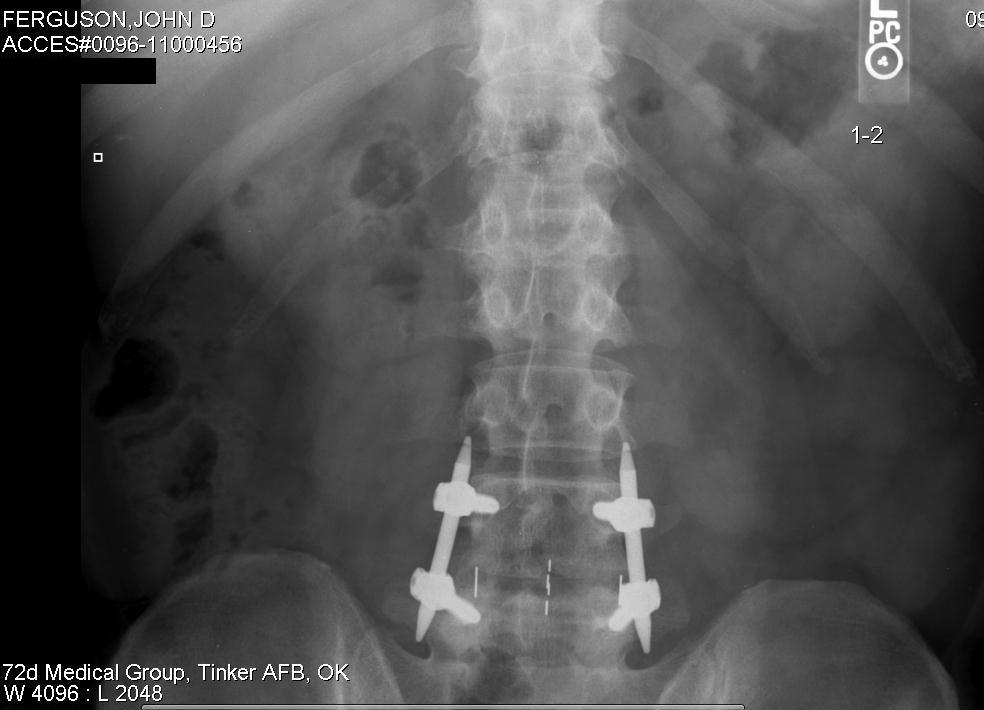

Like you, I know back pain well. I have a dead disc between my L4 and L5 vertebrae, as well as a bone spur that intrudes into my spinal nerve cluster, so I have suffered with shooting sciatica and back pain in various locations for many years - it really limits my mobility and what I can do. I can handle the pain fairly well, but what gets me is that I am limited when playing with my young 6 year old daughter. Of course insurance doesn't pay for disc replacement surgery and I refuse to get my spine fused, but C'est la vie... But as bad as back pain can be, just count your blessings that you don't have a kidney stone - now that's pain!